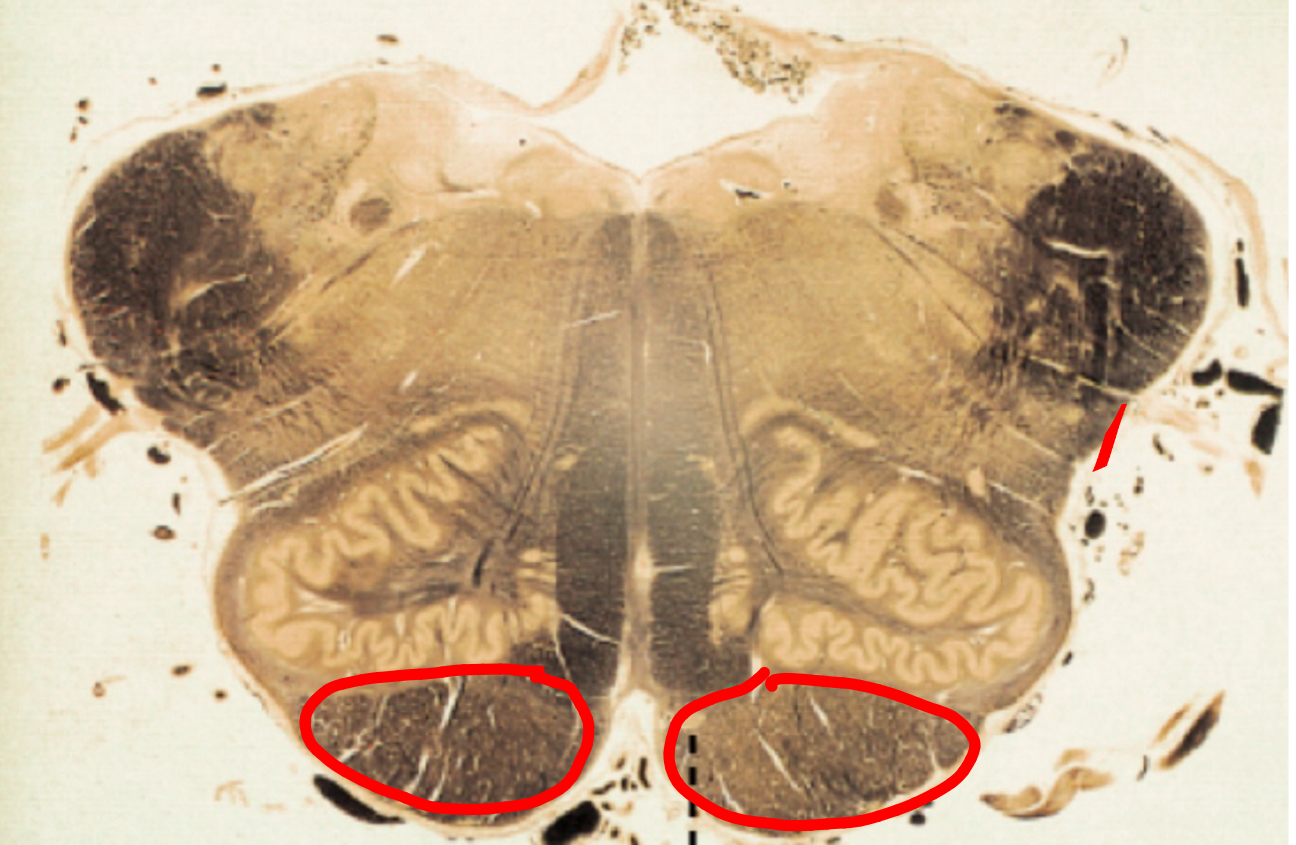

tonsils